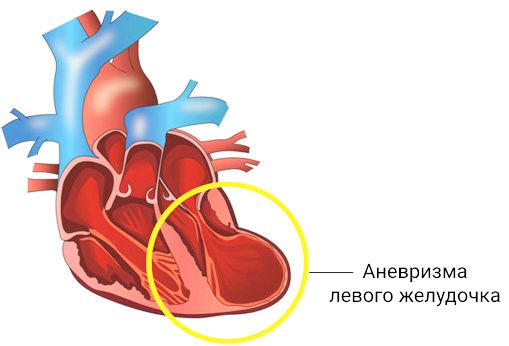

Пороки сердечно-сосудистой системы: виды и признаки